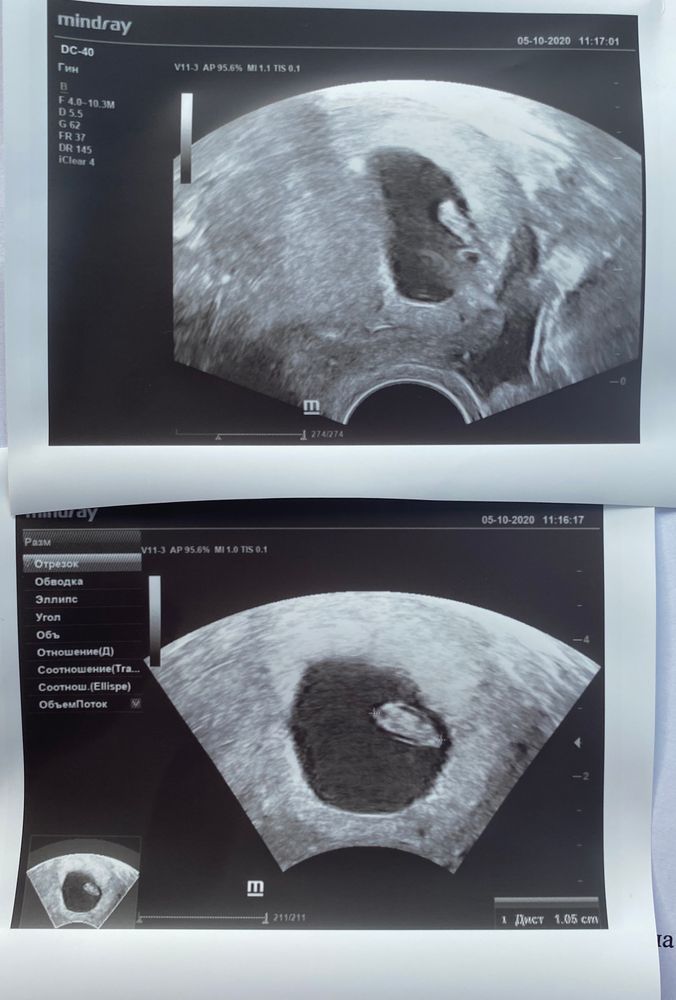

Узи на 30 дпп

Я БЕРЕМЕННА !Девочки, сегодня я была на втором узи. Мой малыш значительно подрос, я видела сердцебиение, врач показала мне будущий позвоночник 🥰 все хорошо! Господи, СПАСИБО!!! Желаю всем девочкам, кто ждёт, такого счастья!

05.10.2020